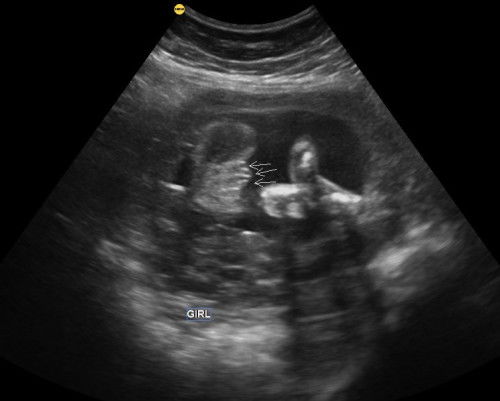

Sapa² ada pengalaman kena induce tak? Saya ada gdm, sekarang kandungan 38minggu 5hari...tapi baby kcik je.. Esok kena serah diri. Ada tak tips2 yg boleh korang kongsi selepas dimasukkan belon untuk cepatkan bukaan sebab sekarang pun masih takda tanda2 nk bersalin tanpa induce..#bantujawap#mohonbantujawabbunda #Needadvice #askmommies